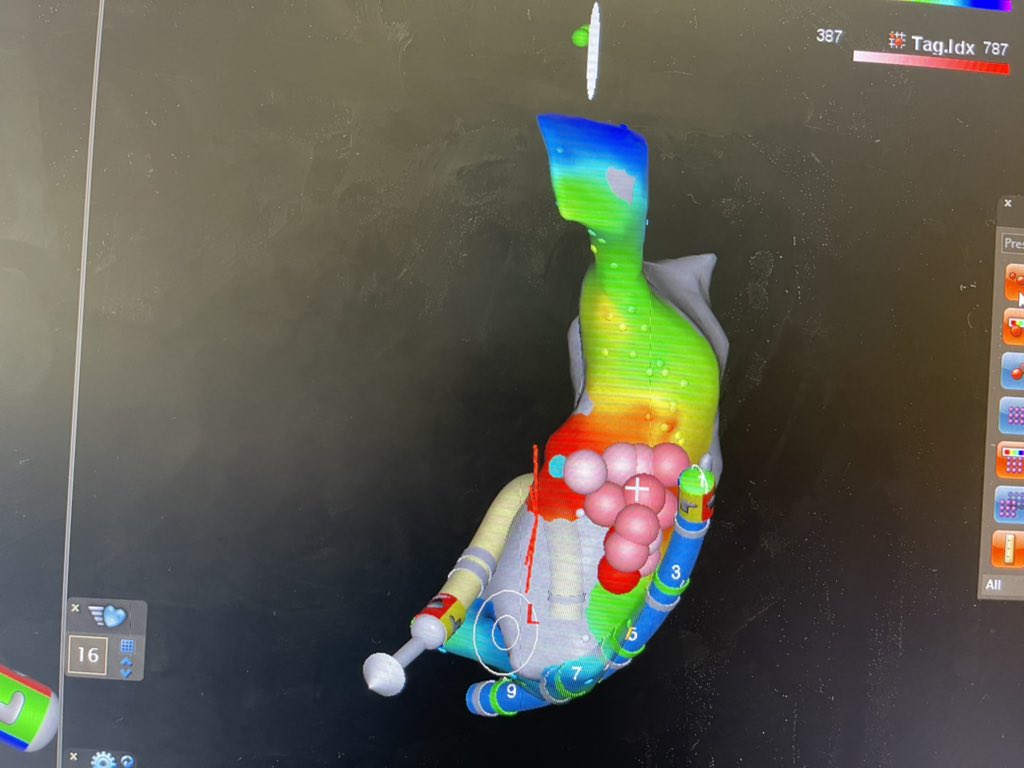

@AatishGarg_EP @VirtuaHealth @HeartVirtua @EPeeps_Bot @HeathHsalt Nice tracings! Nice case of isolated left atrial appendage in atrial fibrillation with exit block after Ostial isolation